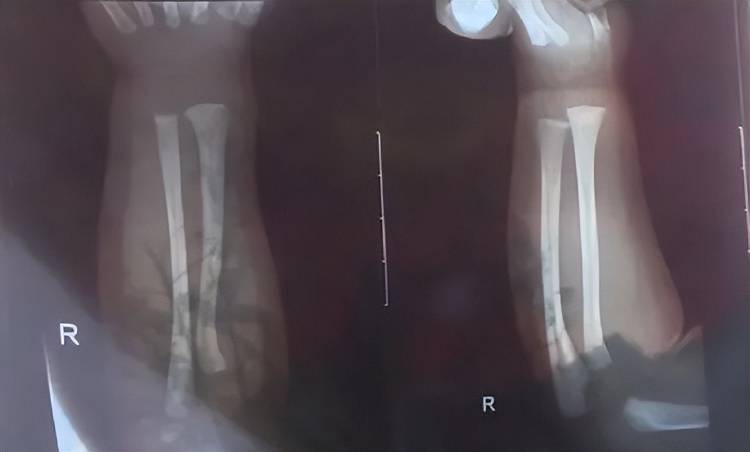

次日上午,孩子被带到附近医院检查,医生诊断发现他右手有两处骨折,第一处为右侧尺骨远端骨折,第二处为右侧桡骨远端骨折,随后医生给他做了石膏固定,“没想到,几天后孩子还被诊断出脑电图异常,医生建议复查虚拟币残币。”

孩子被诊断发现两处骨折